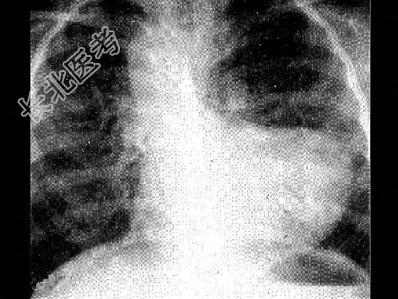

- 单项选择题法洛四联症时X线检查典型表现如图,下列哪一项描述正确 ( )

A、心影大小正常或稍增大,前后位心影呈“靴状”

B、右位主动脉弓

C、肺野充血

D、升主动脉扩大

E、肺动脉段突出